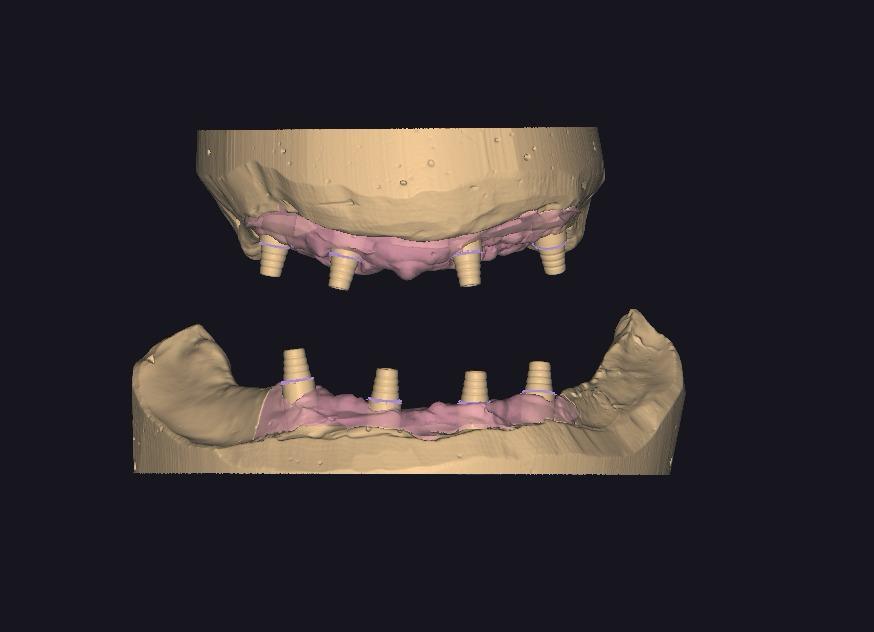

HYBRID PROTEZLER

HYBRID CAM CAM CrCo & TITANYUM PORSELEN BITIM

HYBRID CAM CAM CrCo ARA cOvDE PORSELEN BITIM

HYBRID CAM CAM CrCo TiTANYUM BiTIMSIZ KRON

HYBRID cam cam CrCo BITIMSIZ KRON ARA GOVDE

HYBRID CAM CAM CrCo KOMPOZIT BiTiM

HYBRID CAM CAM CrCo ARA Oyu KOMPOZIT BITIM

HYBRID CAM CAM CrCo TITANYUM ARA GÖVDE PORSELEN BİTİM

VIDALI IMPLANT USTU BAR (HER ABUTMENT BAŞI)